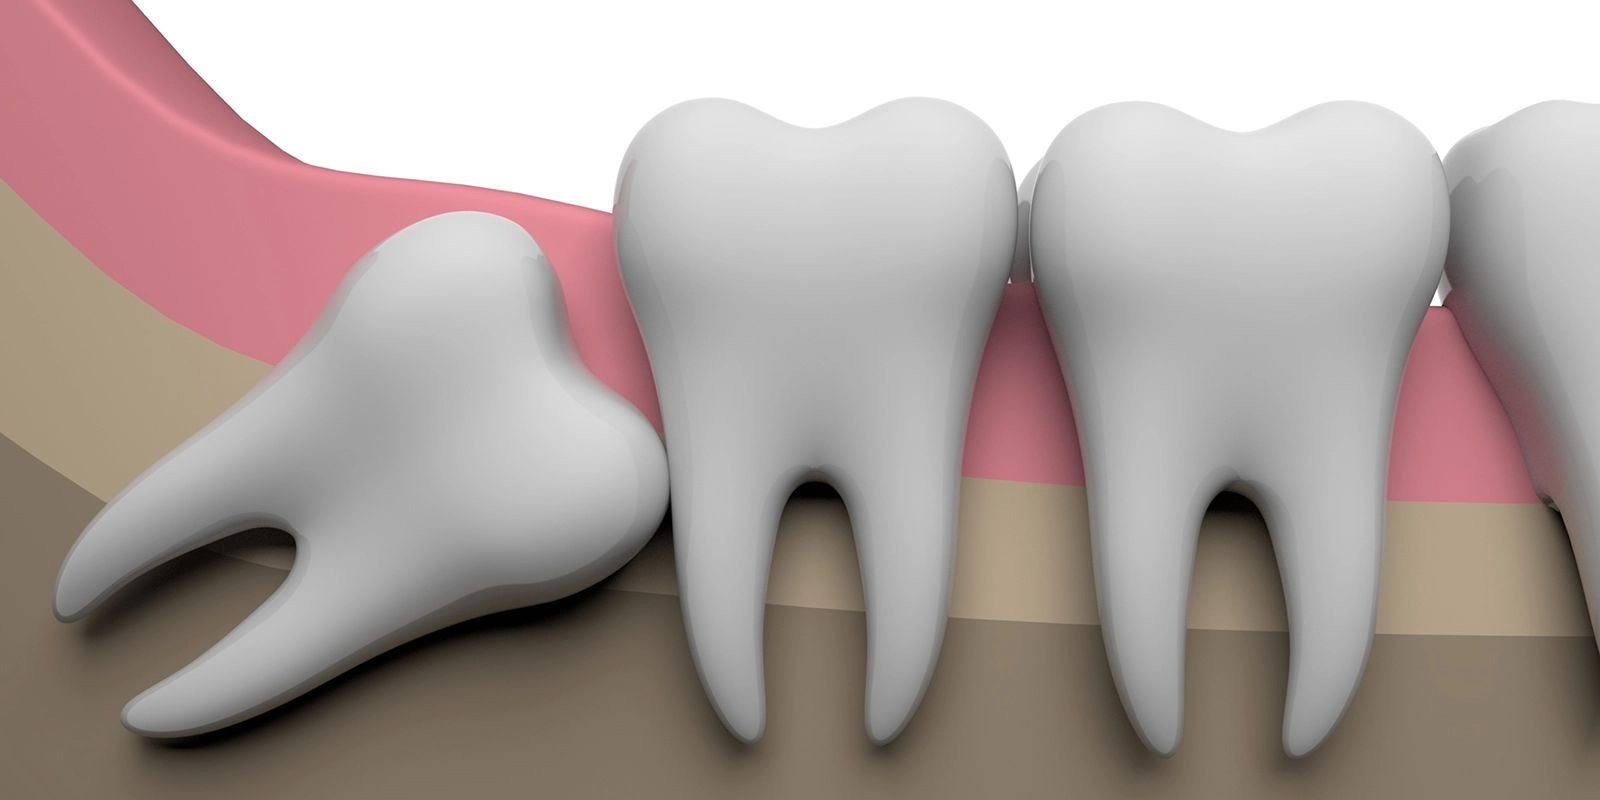

実は現代人の顎は昔の人と比べて小さくなってきているため、親知らずが生えるスペースが不足していることが多く、その結果として真っ直ぐ生えてこないケースが大半を占めているのです。横向きや斜めに傾いたまま歯茎の中に埋まっていたり、一部だけ顔を出していたりすることがよくあり、こうした生え方によってさまざまな問題を引き起こすことがあります。

隣の歯への悪影響

親知らずが横向きに生えていると、手前の第二大臼歯(奥から2番目の歯)を押すことになってしまい、この圧力によって手前の歯が痛んだり、歯並びが悪くなったりすることがあります。

さらに困ったことに、親知らずと手前の歯の間には食べ物が挟まりやすくなるため、せっかく健康だった手前の歯が虫歯や歯周病になるリスクが高まってしまい、最悪の場合は親知らずだけでなく大切な第二大臼歯まで失うことになってしまうこともあるのです。